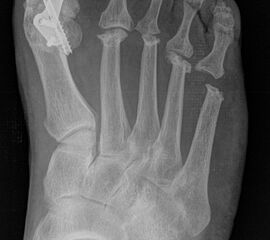

Nach Anamnese und Untersuchung reichen meist konventionelle Röntgenbilder mit Belastung im Stehen a.p. und seitlich ggf. Schrägaufnahmen zur Beurteilung und Indikationsstellung aus. CT oder MRT sind in der Regel nicht erforderlich, im Einzelfall aber ergänzend sinnvoll. Szintigraphie und Sonographie spielen bei der Indikationsstellung und Operationsplanung eine untergeordnete Rolle.

Zum Lesen der Bildbeschreibung und zur Vollansicht bitte die Bilder anklicken.